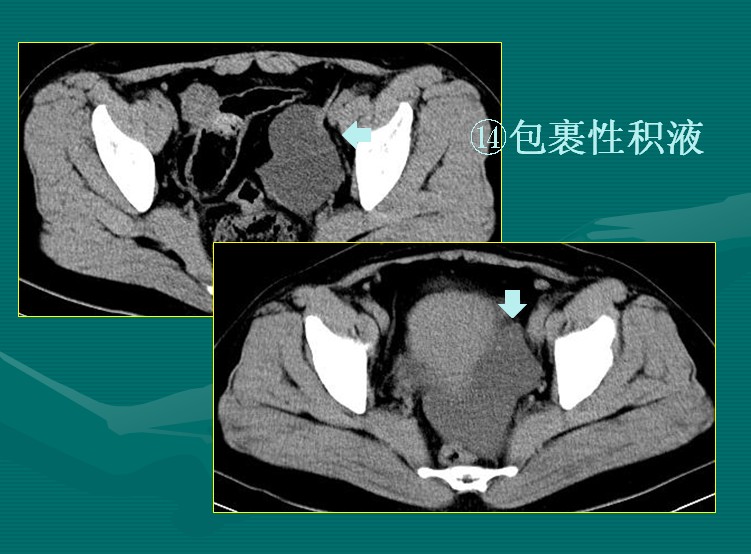

包裹性积液也是一种假性囊肿,见下图